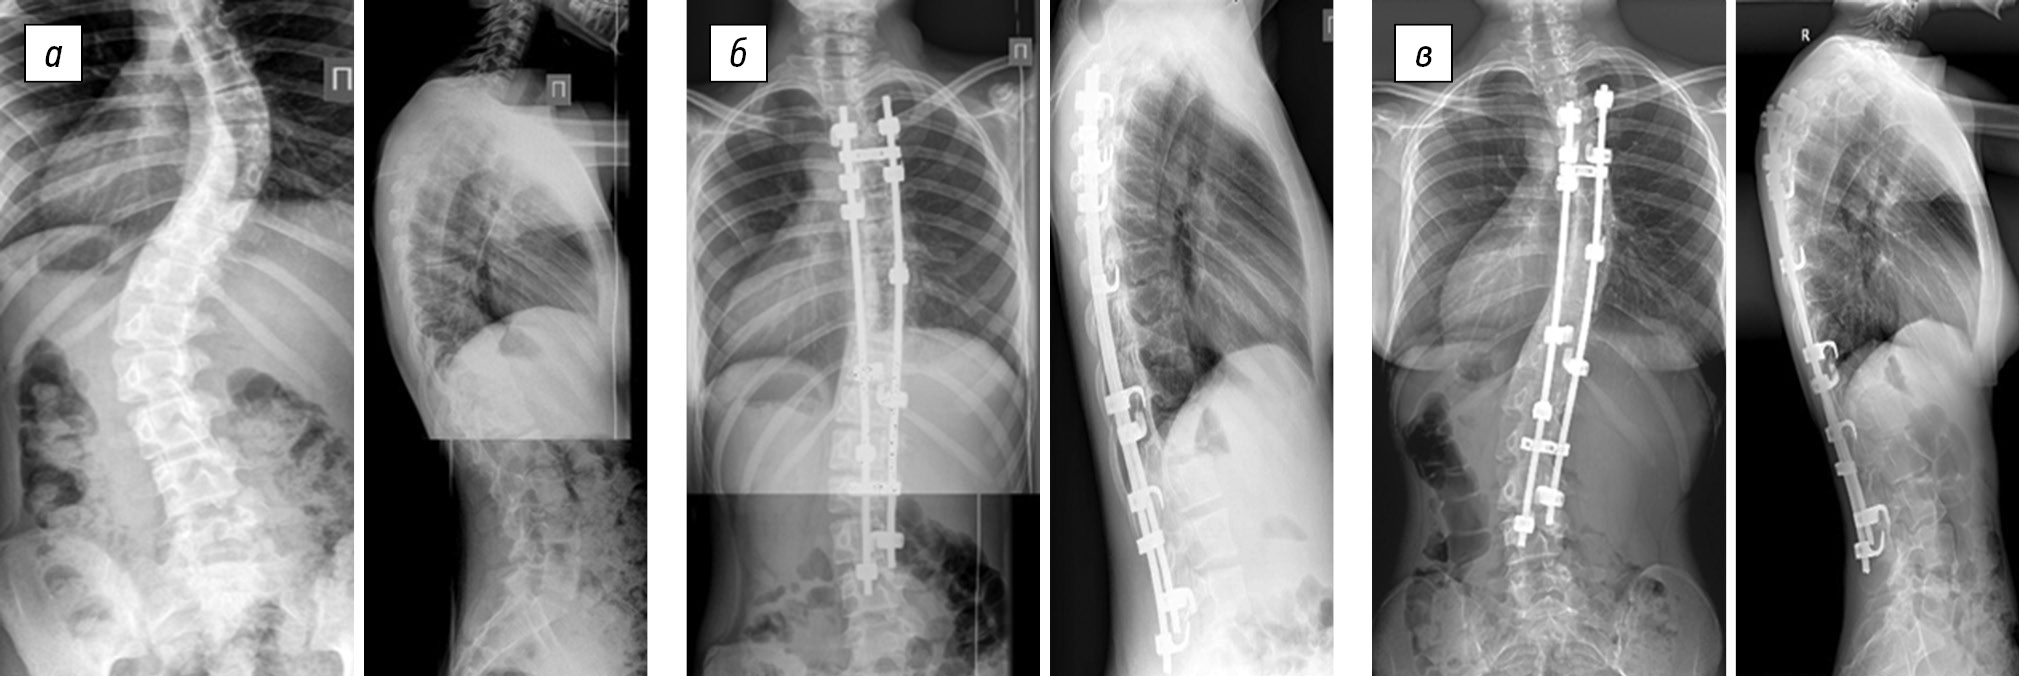

In group 1 (Table 1), the preoperative size of the thoracic scoliotic curve was 61.0 ± 13.6°, and the postoperative thoracic scoliotic curve was reduced to 18.5 ± 10.4° (p < 0.05). The value of the primary correction was 42.5 ± 9.1°, which was found in 70.8 ± 12.2% of the cases (p < 0.05). Postoperative progression was on average 5.9 ± 3.2°, which was found in 14.3 ± 8.3% of the cases (Fig. 1). The average patient age was 12.6 ± 0.7 years, and the average duration of postoperative follow-up was 46.5 ± 25.6 months.

Fig. 1. Radiographs of a 13-year-old patient in two views: a — preoperative image of the right-sided thoracic scoliotic deformity of IV degree (74° according to Cobb) with lumbar anti-curvature (47°), with thoracic kyphosis of 24° and lumbar lordosis of 67°; b — surgical correction of scoliotic deformity of the spine using hybrid fixation without ventral intervention results in main thoracic curve of 30°; lumbar anti-curvature of 10°, thoracic kyphosis of 18°, and lumbar lordosis of 60°; c — X-ray control 3 years after the surgery revealed main thoracic curve of 46°, lumbar anti-curvature of 10°, thoracic kyphosis of 18°, and lumbar lordosis of 76°